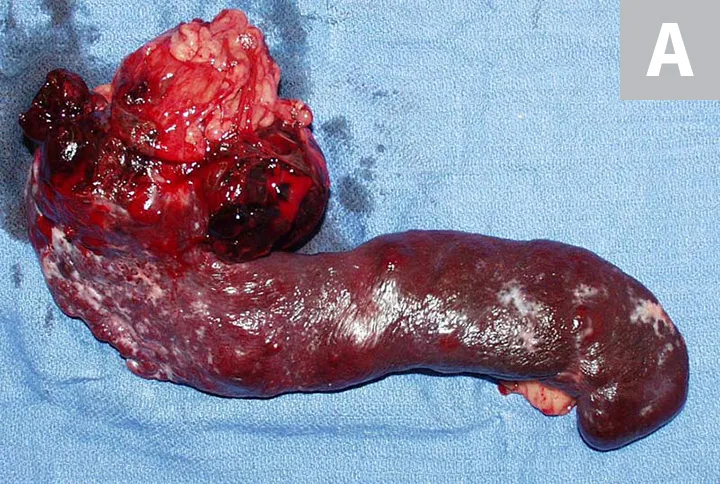

Primary noncutaneous HSA involving the head of the spleen (A) and the right auricle (B, arrowheads). Images courtesy of Laura Garrett, DVM, DACVIM (Oncology), and Louis-Philippe de Lorimier, DVM, DACVIM (Oncology)